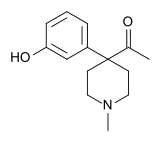

4-Phenylpiperidines

Others

Structures

| Other phenylpiperidines | |||

|---|---|---|---|

Alvimopan Alvimopan |

Loperamide Loperamide |

LS-115509 LS-115509 |

Picenadol Picenadol |